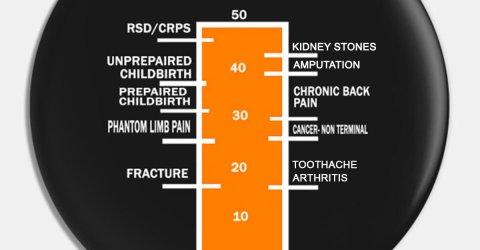

Endless pain cannot crush one tiny fighter’s spirit (7 Photos)

In the middle of the night, Jay’lee began to cry. Jessica jumped out of bed, her maternal instincts on high alert.

As Jessica sleepily changed her daughter’s diaper in the darkness, she couldn’t have known what was causing Jay’lee to cry. She didn’t know then, that her daughter was suffering… that she was in excruciating pain…